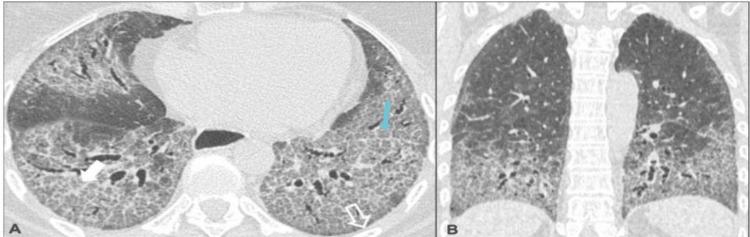

Introduction Interstitial lung diseases (ILDs) primarily affect the interstitium, an alveolar wall tissue between the capillary endothelium and the alveolar epithelium. The term 'interstitial,' however, is misleading since alveolar spaces, peripheral airways, and vessels can be involved in most of these disorders.They often require a multidisciplinary diagnosis i.e., an integration of clinical, radiological, and pathological findings. A chest radiograph is relatively insensitive because of nonspecific patterns. Generally, these disorders can progress to irreversible pulmonary fibrosis and are an important cause of morbidity and mortality. It is critical to make a prompt and accurate diagnosis of the underlying causes so that patients can be managed appropriately. ILD is subdivided into idiopathic interstitial pneumonia, of which idiopathic pulmonary fibrosis (IPF) is one subset, and diffuse parenchymal lung diseases, which may be secondary to a variety of occupational or environmental exposures or others. They can complicate multiple rheumatic or connective tissue diseases (CTDs). Apart from ILD, other forms of lung damage involving the pleura, vasculature, airways, and lymphatic tissue can complicate CTDs. Aims  Aims include studying the role of high-resolution computed tomography (HRCT) in diagnosing various ILDs based on morphologic patterns, evaluating the correlation between ILD and various connective tissue disorders and the prevalence of complications in such patients, and evaluating the association of smoking with various ILDs. Methods This is a retrospective study in which HRCT thorax was performed on a 128-slice Philips CT scanner machine on 50 patients from December 2020 to February 2022 in SVP Hospital, Ahmedabad. No age or gender bias was followed. Result Out of 50 patients studied, 19 (38%) patients had the usual interstitial pneumonia (UIP) pattern and 12 (24%) had the nonspecific interstitial pneumonia (NSIP) pattern. These two were the most common among all ILD patterns. Other patterns found were hypersensitivity pneumonitis (5; 10%), respiratory bronchiolitis-related ILD (3;6%), and organizing pneumonia (2; 4%). In nine patients, the morphologic pattern was either subtle (3; 6%) or mixed (6; 12%), and the final diagnosis remained inconclusive; patients were advised clinical correlation and biopsy. Eleven (22%) patients had a history of smoking. Among smokers, the most common pattern was UIP while all patients with respiratory bronchiolitis (RB) ILD had a history of smoking. Fourteen (28%) patients showed a positive association with CTD. Among them, rheumatoid arthritis (RA) was the most common CTD and the most common pattern among RA patients was UIP. Ten (20%) of patients developed pulmonary arterial hypertension, of which two patients who had connective tissue disorder developed pulmonary arterial hypertension at a young age (24 years). The rest of the patients who developed pulmonary arterial hypertension were above 45 years of age. Among these, two were smokers. Conclusion HRCT plays an important role in the diagnosis of ILD on the basis of various morphological patterns. CTD plays a significant role in the development of ILD. UIP is the most common ILD among patients with a smoking history and RA. NSIP Is the most common in patients with CTD other than RA. Pulmonary arterial hypertension (PAH) develops early in patients with CTD. There is a significant risk of the development of PAH in patients with chronic ILD.

在研究的50例患者中,19例(38%)表现为普通型间质性肺炎(UIP)模式,12例(24%)表现为非特异性间质性肺炎(NSIP)模式。这两种是所有ILD模式中最常见的。发现的其他模式包括过敏性肺炎(5例;10%)、呼吸性细支气管炎相关的ILD(3例;6%)和机化性肺炎(2例;4%)。9例患者的形态学模式不明显(3例;6%)或为混合型(6例;12%),最终诊断仍不明确;建议患者进行临床关联和活检。11例(22%)患者有吸烟史。在吸烟者中,最常见的模式是UIP,而所有呼吸性细支气管炎(RB)ILD患者都有吸烟史。14例(28%)患者显示与CTD呈正相关。其中,类风湿关节炎(RA)是最常见的CTD,RA患者中最常见的模式是UIP。10例(20%)患者发生了肺动脉高压,其中2例患有结缔组织病的患者在年轻时(24岁)发生了肺动脉高压。其余发生肺动脉高压的患者年龄在45岁以上。其中,2例为吸烟者。